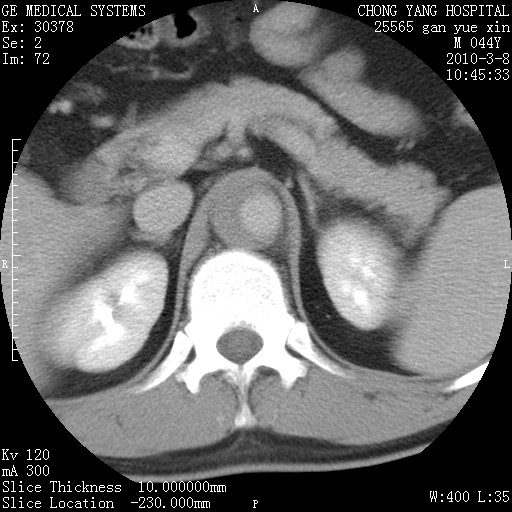

标题: CT24940:主动脉增强,典型病例。 [打印本页]

标题: CT24940:主动脉增强,典型病例。

夹层动脉瘤。

动脉夹层

夹层动脉瘤,典型

主动脉夹层。

动脉夹层的分型:

⒈debakey分型:根据主动脉夹层累及部位,分为三型:ⅰ型:原发破口位于升主动脉或主动脉弓部,夹层累及升主动脉、主动脉弓部、胸主动脉、腹主动脉大部或全部,少数可累及髂动脉。ⅱ型:原发破口位于升主动脉,夹层累及升主动脉,少数可累及部分主动脉弓。ⅲ型:原发破口位于左锁骨下动脉开口远端,根据夹层累及范围又分为ⅲa,ⅲb。ⅲa型:夹层累及胸主动脉。ⅲb型:夹层累及升主动脉、腹主动脉大部或全部。少数可累及髂动脉。

⒉stanford分型:a型:夹层累及升主动脉,无论远端范围如何。b型:夹层累及左锁骨下动脉开口以远的降主动脉。

夹层动脉瘤,少量胸水

夹层动脉瘤;左侧少量胸腔积液。

典型主动脉夹层。